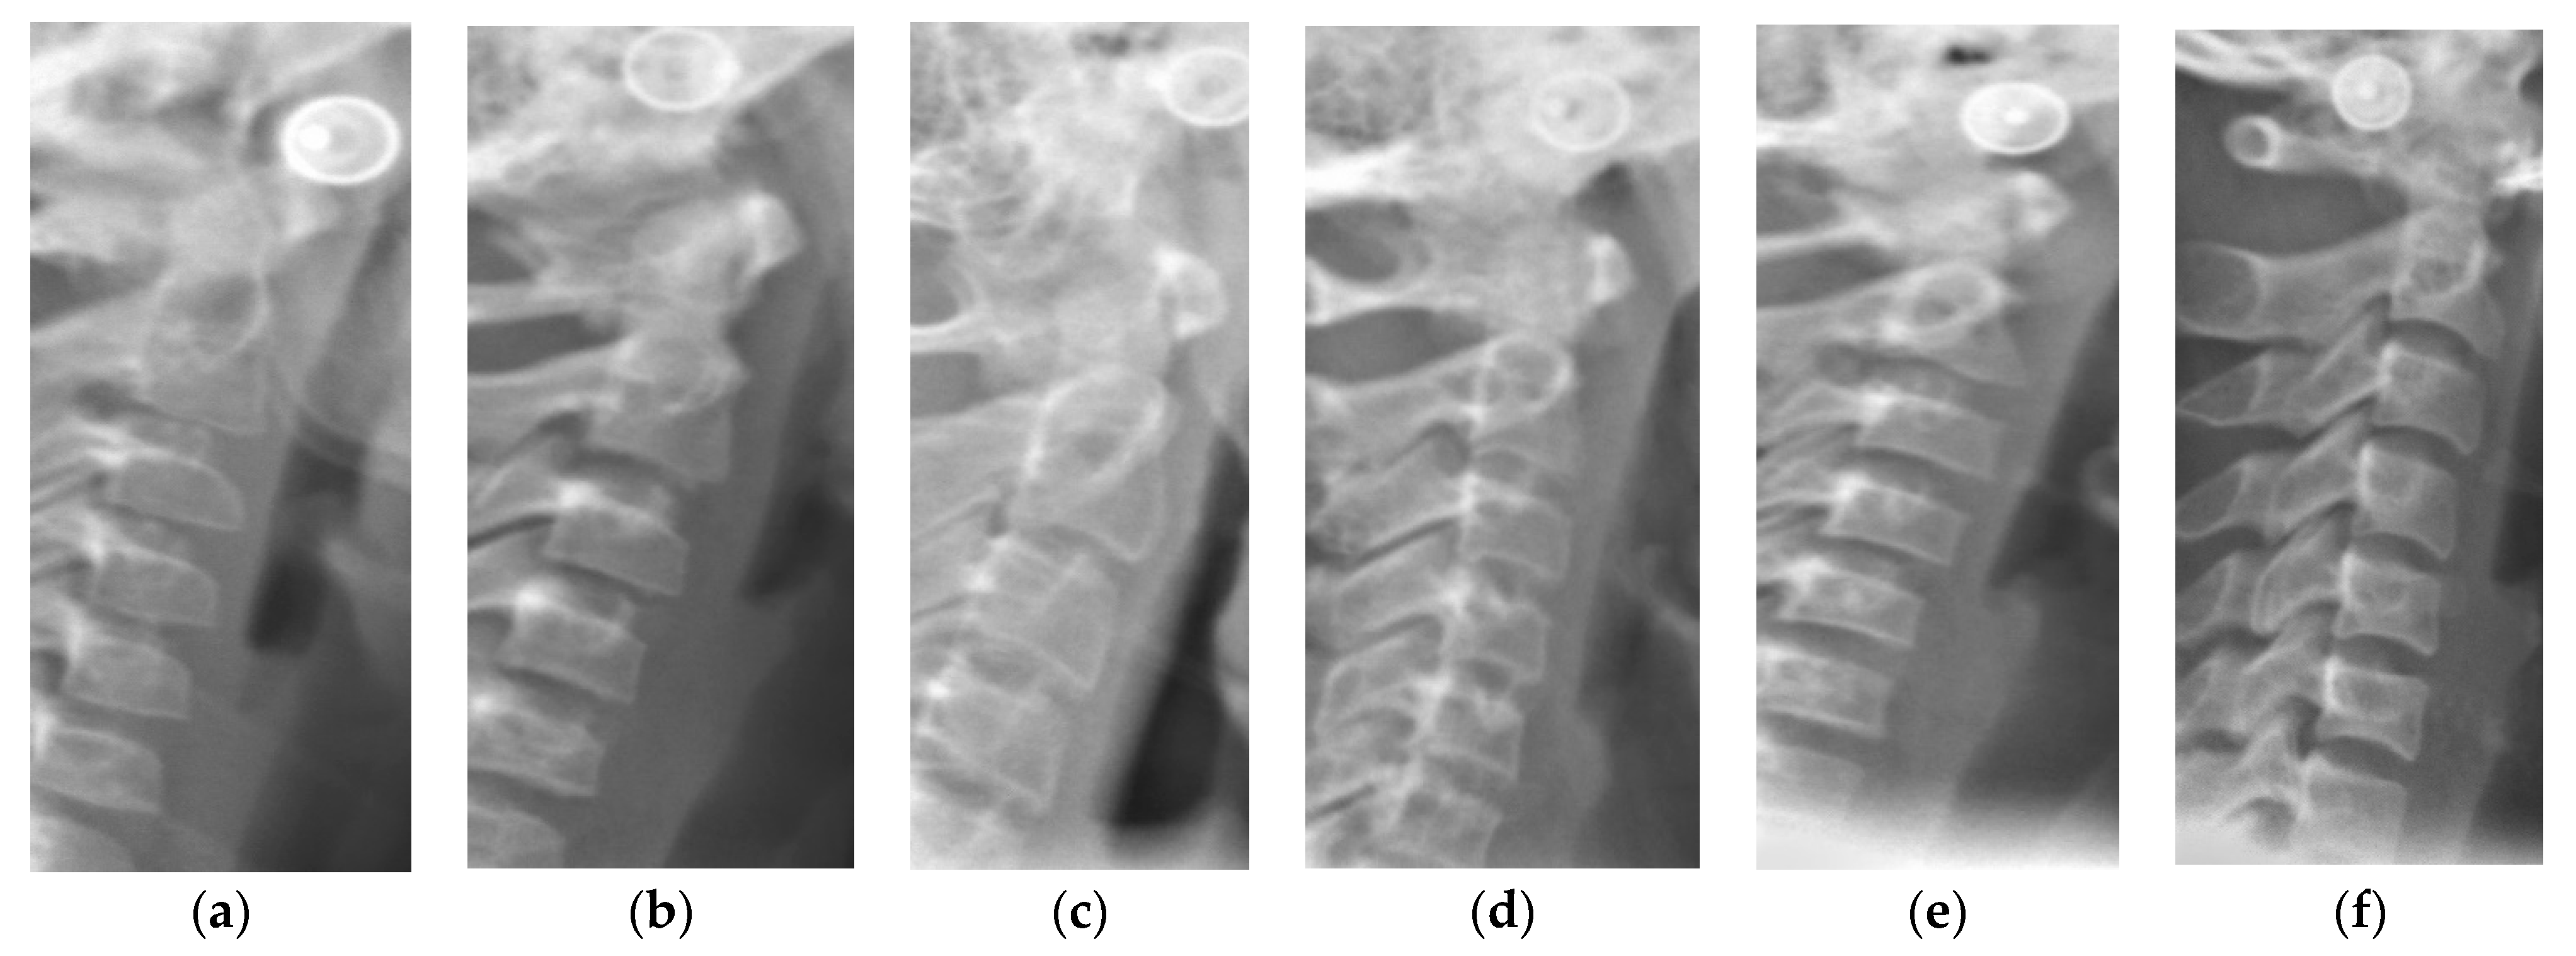

Lateral cephalograms were taken for all the recruited subjects with radiographic exposure at 80 kV, 9 mA for 1.25 s as a part of the routine orthodontic diagnostic and treatment protocol, thus avoiding the ethical concerns of additional radiation exposure as in Handwrist radiographs. All the radiographs were taken using the same digital X-ray equipment, Kodak 8000 panoramic, and cephalometric system. Radiographs were evaluated using Apteryx Imaging software. Two examiners, who were blinded to the patient’s personal and clinical details, interpreted the radiographs and categorized them into 3 groups depending on the cervical vertebral maturation staging (CVS1-CVS6) as proposed by Baccetti et al. [12] (Figure 1). Inter-examiner reliability and intra-examiner reliability were estimated using Kappa statistics. The groups representing different skeletal maturity stages are as follows:

Figure 1. Schematic representation and examples of different cervical maturity stages. CVS: cervical vertebral staging. (a) CVS1: Flat lower borders of all the three vertebrae. Trapezoidal body of C3 and C4; (b) CVS2: Concavity present at the Lower border of C2. No change in shape of bodies of C3 and C4; (c) CVS3: Concavities present at Lower borders of both C2 and C3. C3 and C4 bodies may be either trapezoid or rectangular horizontal in shape; (d) CVS4: Concavities present at Lower borders of C2, C3, and C4. C3 and C4 bodies are rectangular horizontal in shape; (e) CVS5: Concavities present at Lower borders of C2, C3, and C4. Either one of the bodies of C3 and C4 has square shape others remain rectangular; (f) CVS4: Concavities present at the lower borders of C2, C3, and C4. At least one of the bodies of C3 and C4 attained rectangular elongated in shape and the bodies of the other cervical vertebra remain squared.